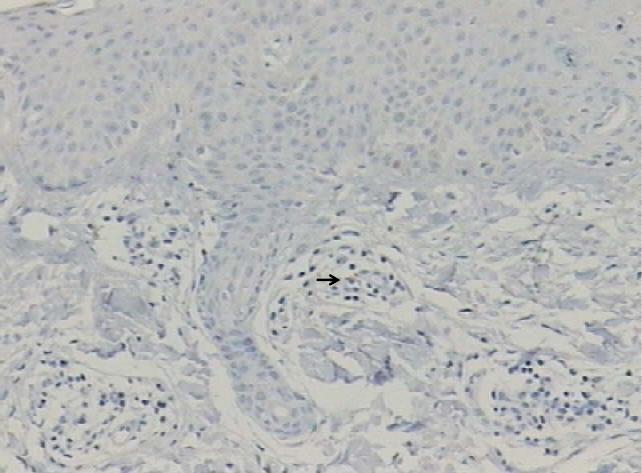

CD8 Raras 1 12,5 0 0,0 0 0,0 0,7617

Leve 6 75,0 7 77,8 3 75,0

Moderado 1 12,5 1 11,1 1 25,0

Intenso 0 0,0 1 11,1 0 0,0

Total 8 100,0 9 100,0 4 100,0